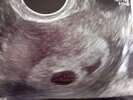

Wyniki będę mieć jutro o 11 pielęgniarka powiedziała że jeśli nie wykaże nic pierwsze pobranie to mam nie przychodzić na następne następnego dnia czy to prawda?... Przesyłam zdjęcie USG może wy widzicie tą małą fasolkę 😔❤️

Załączniki

• IMG_20220601_081443.jpg

IMG_20220601_081443.jpg

1,5 MB · Wyświetleń: 147